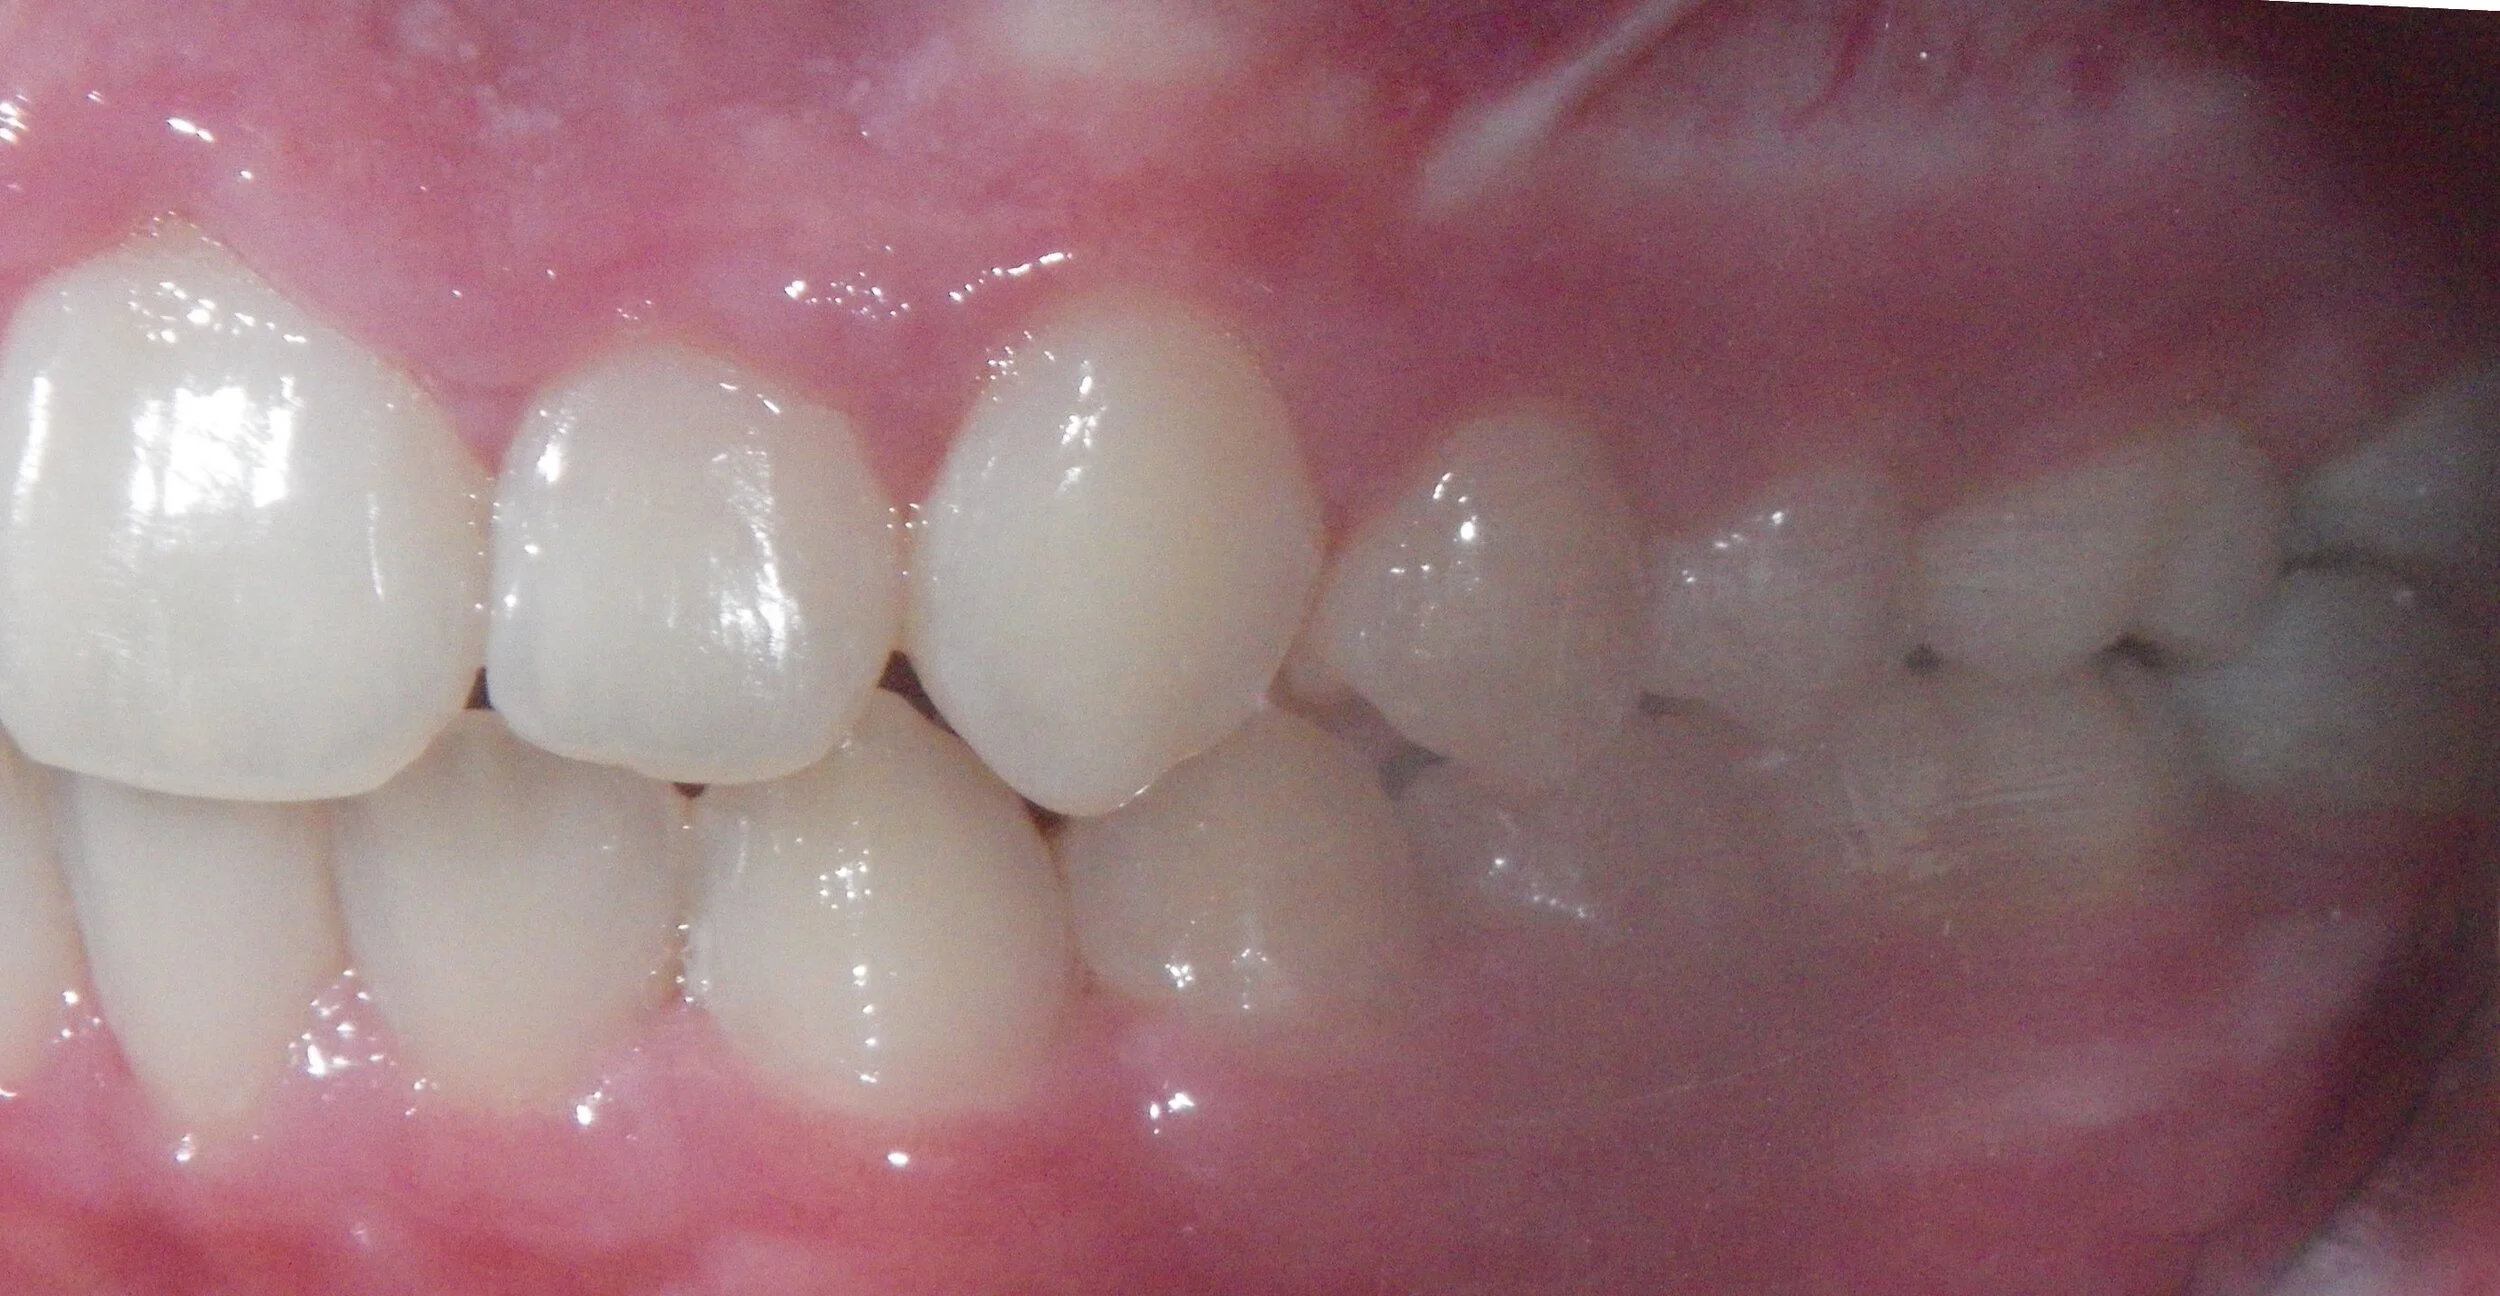

Phase I can be used to help change unfavorable growth or to make room so all the adult teeth have room to erupt. Here, we used Phase I to make room for the adult canines and followed up with Phase II treatment to a get a great esthetic and functional result!